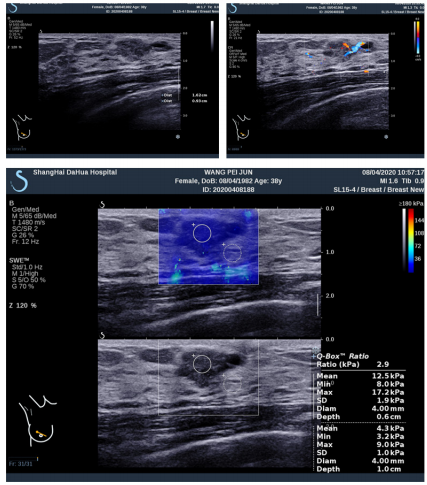

图 3 1 例 44 岁女性经手术病理证实为乳腺病

注:a,B 超 图 像 显 示 一 个 2.8cm 的 非 肿 块 病 变, 评 估 为 BIRADS 4a 级(箭头);b,超见右乳头内上方不规则低回声区, 范 围 16mm×9mm,BI-RADS 评 级 为 4A; 和 c,SWE 图 像 显 示: Emean:12.5KPa,Emax:17.2KPa。